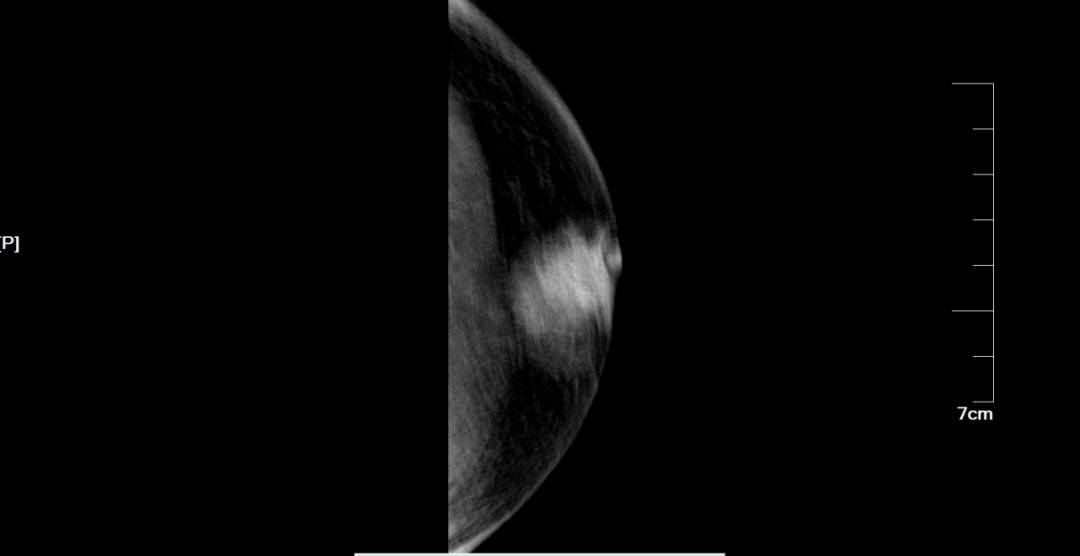

钼靶:左乳头后可见一不规则肿块影,边缘毛糙,边界不清,大小约为27mm×24mm×24mm,其内可见微钙化,邻近乳晕区皮肤增厚,乳头内陷。

图5 左乳钼靶示左乳头后方不规则肿块影

乳腺钼靶提示:左乳肿块影,考虑恶性病变,建议手术 BI-RADS 5类